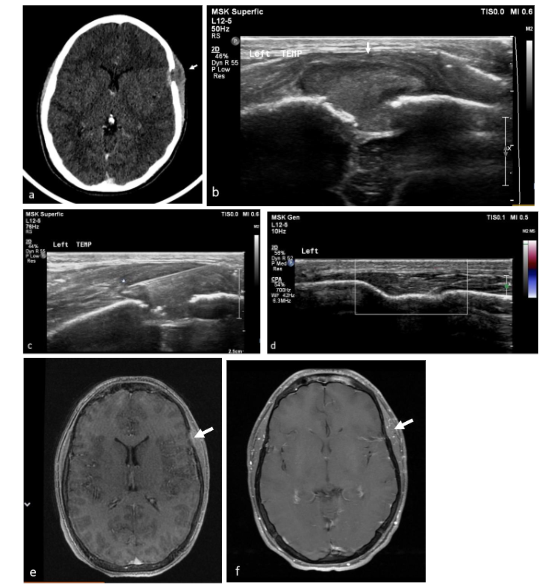

Regression of lesions occurred in 4 cases. In 2 cases regression was spontaneous, one lesion regressed completely and the second decreased in size while the patient awaited surgery, yet it was nevertheless resected. Biopsy initiated complete regression in 2 cases, the first case post-surgical biopsy and the second post FNB. The FNB case was a temporal lesion with CNS risk, yet complete regression did not require further treatment and no recurrence was reported in 17 years of follow up.

Regression of lesions occurred in 4 patients (11%). Two spontaneously and 2 post biopsies. In one of these patients, the lesion was a temporal bone lesion, a CNS risk lesion, and yet since it regressed spontaneously post FNB the patient was not treated and is disease free in 17 years follow up. Previous studies have documented similar spontaneous remissions of LCH bone lesions, including those affecting the calvaria. Regression has also been noted following biopsy, suggesting that biopsy could stimulate healing. The triggers for Langerhans cell proliferation and the factors that inhibit this process remain unclear. One hypothesis suggests that spontaneous resolution occurs due to a breakdown in self-tolerance, leading to the activation of immune effector cells that target and kill proliferating cells. A similar mechanism has been proposed for halo nevus. Consequently, some authors advocate for a short observation period as part of the initial management strategy for solitary calvarial LCH lesions to avoid unnecessary surgical intervention. Haupt et al. observed that often in isolated bone lesions, simple curettage during the diagnostic biopsy resulted in healing, therefore further intervention may not be necessary.